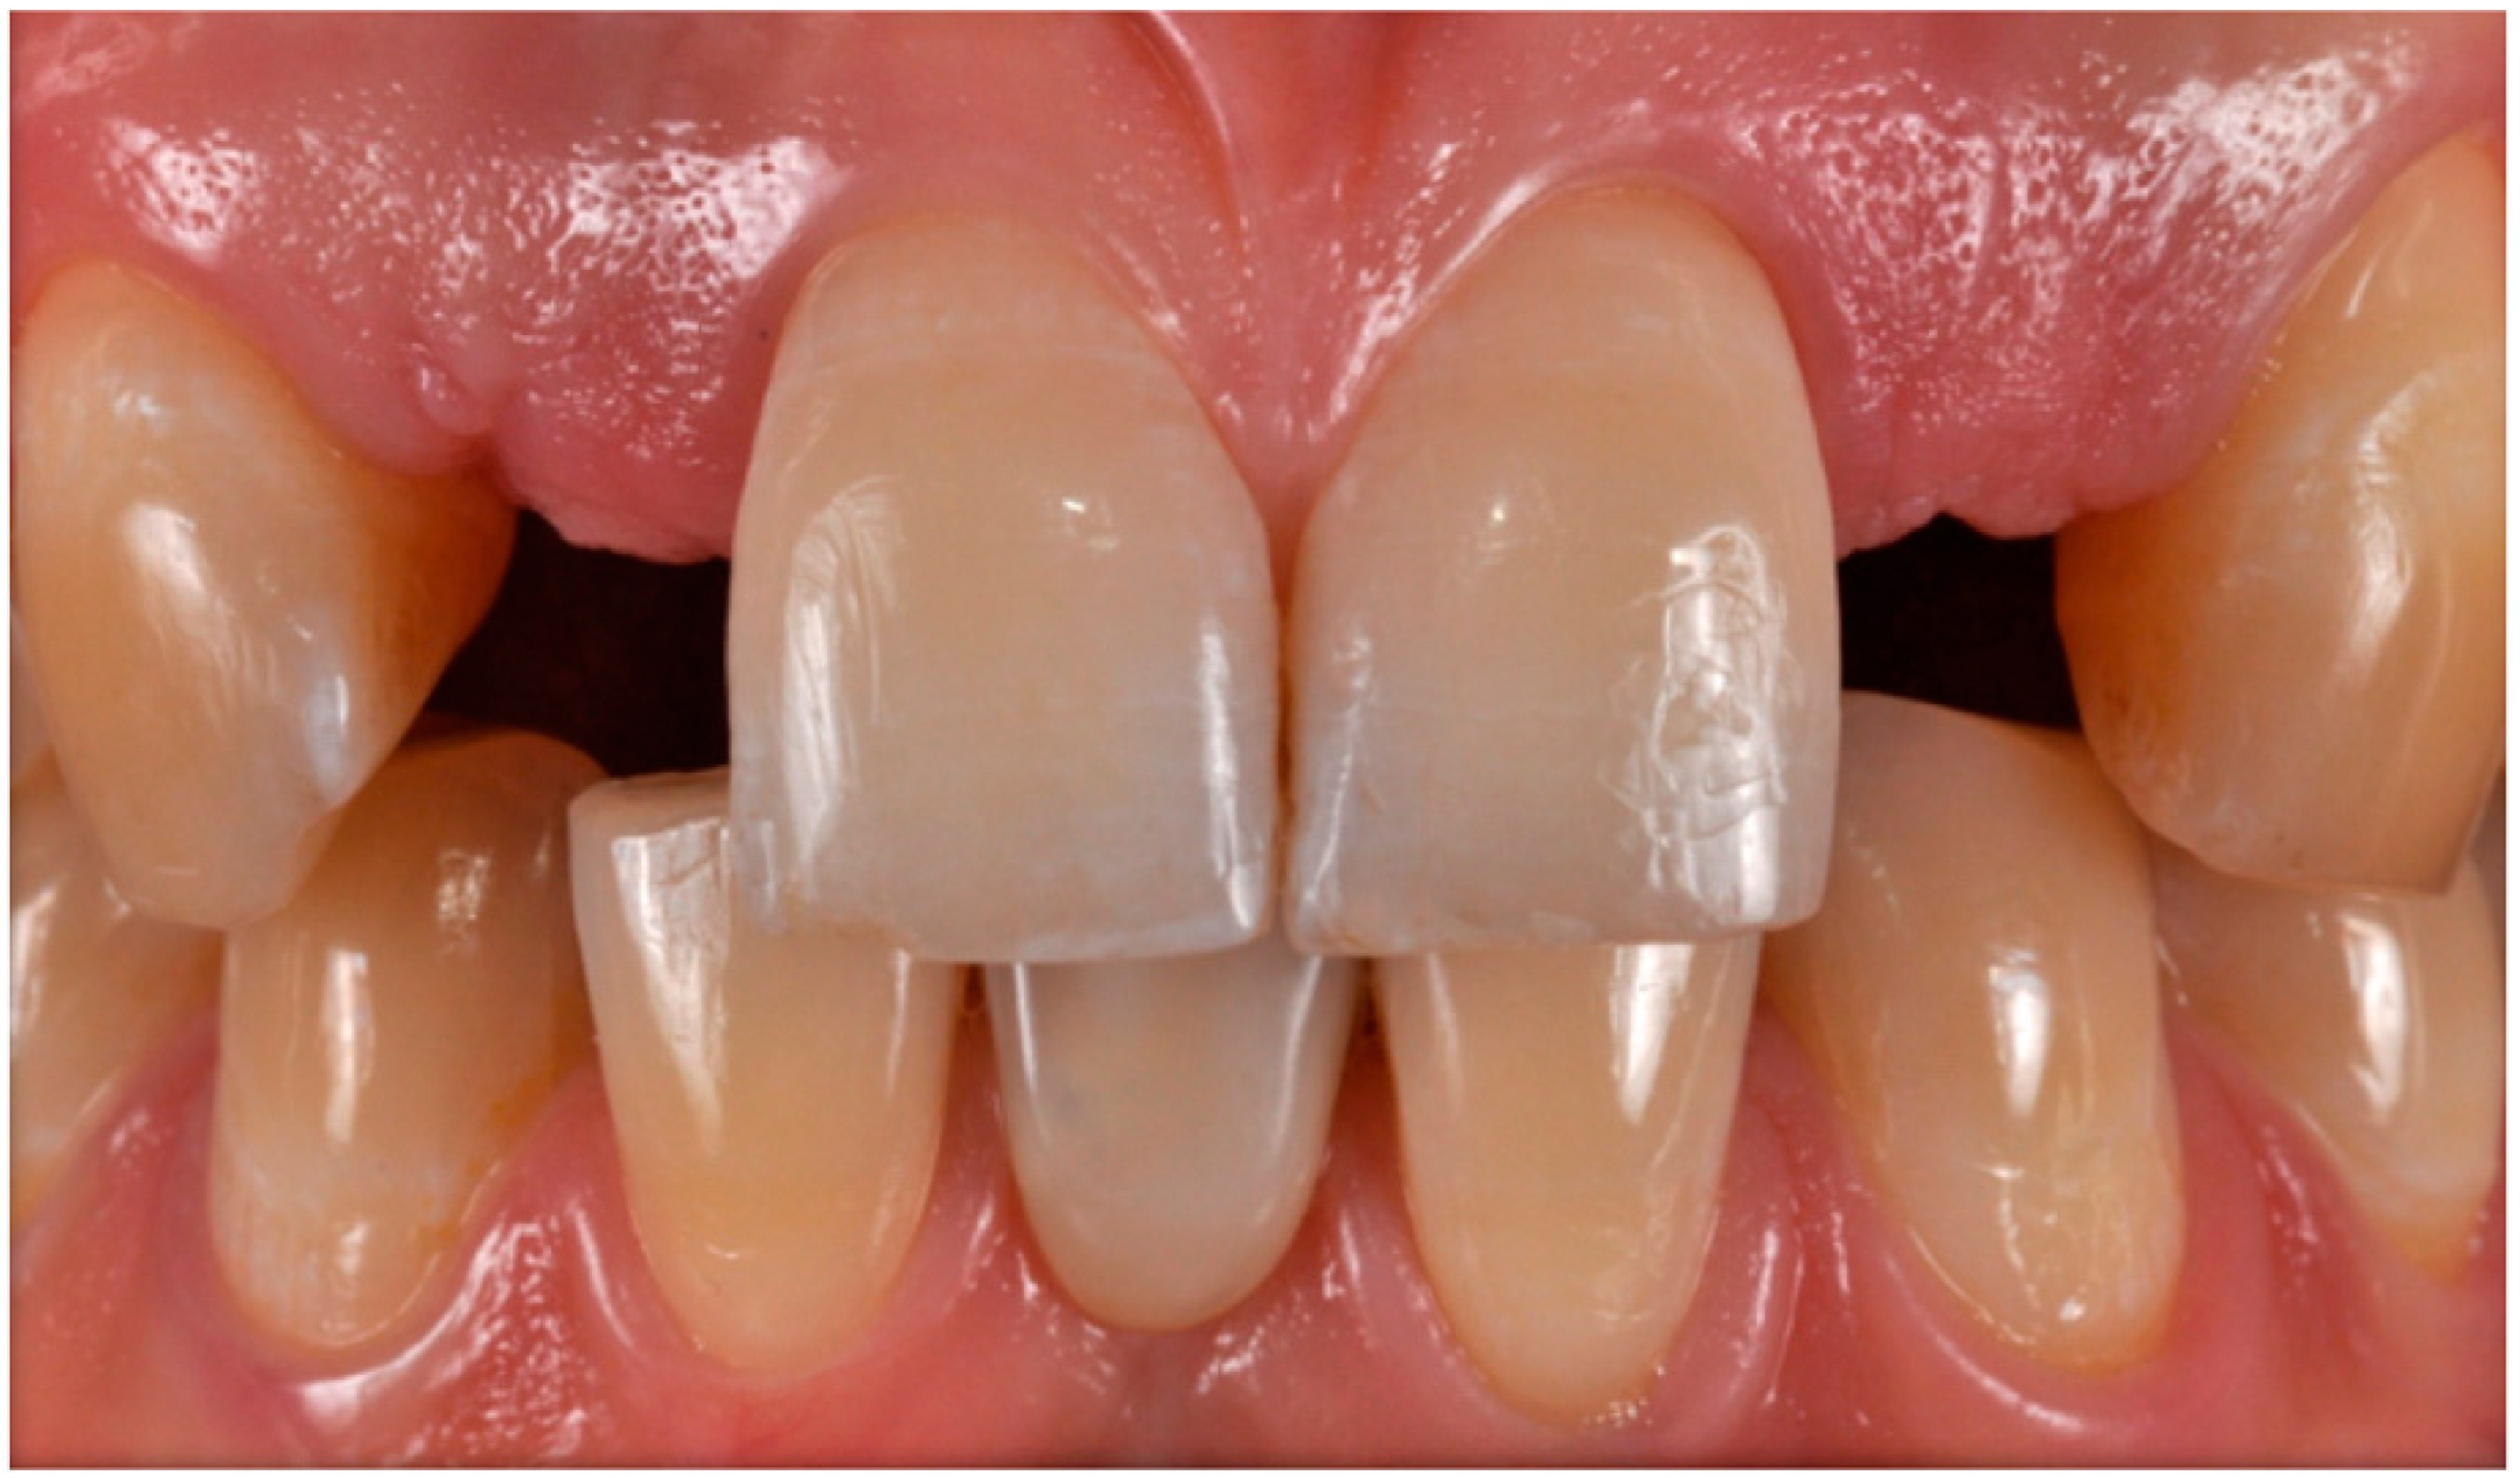

The case describes rehabilitating two congenitally missing lateral incisors in a young patient (38 years old) undergoing orthodontic treatment to create the necessary space for implant placement (Figure 1 and Figure 2). Two fibre-reinforced composite Maryland bridges (Tender Fiber Quattro—Micerium) were utilised for provisional rehabilitation (Figure 3, Figure 4 and Figure 5). Two Osstem TSIII 3.5 × 10.0 implants (1.5 mm subcrestal), two straight Osstem Zirconia abutments, and two-layered lithium disilicate crowns were employed for the definitive restoration (Figure 5, Figure 6, Figure 7, Figure 8, Figure 9, Figure 10, Figure 11, Figure 12, Figure 13, Figure 14, Figure 15, Figure 16, Figure 17, Figure 18, Figure 19 and Figure 20) [8,9]. The dental implant position was planned after a three-dimensional radiographic analysis in a prosthetically guided way. Patient rehabilitation was performed with an immediate post-surgery provisional (Maryland-type, cemented with a resinous cement) application. Subsequently, a delayed loading of the new provisional dental implant was retained (cemented with zinc oxide eugenol cement) and finally, definitive crowns (cemented with a definitive resinous cement) on Osstem® abutments were installed (3 months).

Figure 1. Agnesia of 1.2–2.2. Initial case; front view.

Figure 19. Completed case.

Prosthesis 05 00081 g019

Figure 20. Aesthetic integration: frontal (a) and lateral (b) views.

Prosthesis 05 00081 g020